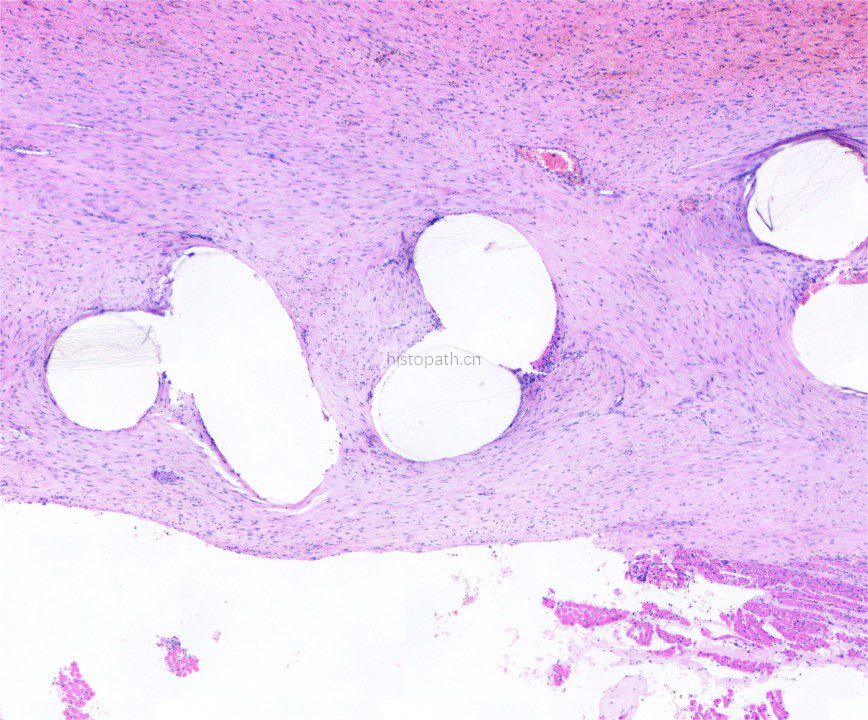

使用德国EXAKT切磨系统进行硬组织切片,特别是对于含有金属这类植入物的组织,是一种精确的组织切片技术。

各类尺寸的含金属植入物骨、牙齿、血管等硬组织样本脱水,7200树脂浸润包埋,后期用标准尺寸(25mm*75mm)的树脂片进行切磨片处理。

将包埋好的硬组织树脂块,用EXAKT 硬组织切片机先切一个200um的厚片,然后再通过EXAKT 硬组织磨片机将其磨到20-30um薄片,样本是已经硬组织包埋好的含金属的动物样本。

针对不同的病理阅片指标需求,行HE染色、Masson染色、亚甲基蓝-酸性品红染色、VG染色、Movat染色等。